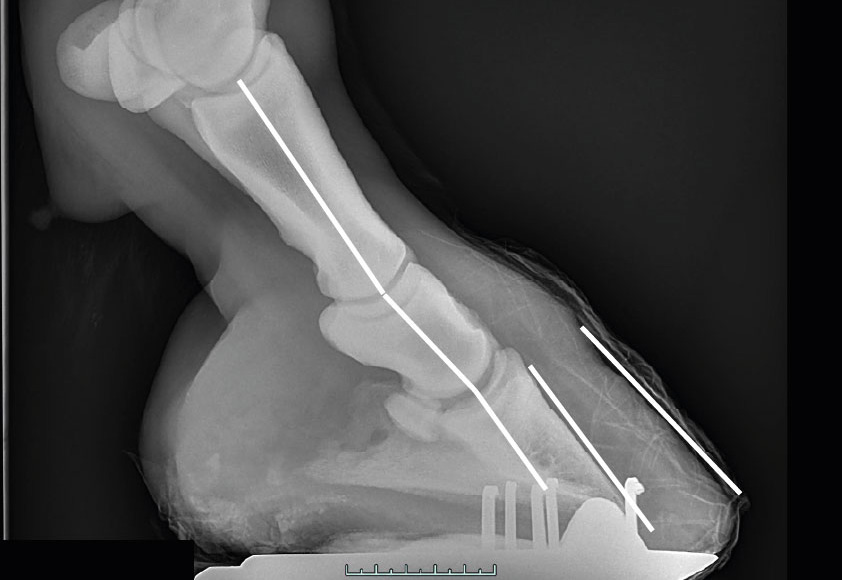

Eine Analyse von etlichen Röntgenaufnahmen zeigte eindrucksvoll, wie sich die Knochen der Knochensäule einer zur Seite verschobenen Belastung anpassen können. Die folgende Aufnahme zeigt beispielhaft anhand der weißen Linie, wie sehr zur Seite versetzt die Kräfte in den einseitigen Huf eingeleitet werden und wie sich die Knochen der Belastung angepasst haben.

Röntgenbild eines Vorderhufes von hinten (palmar) mit einer einseitigen Mehrbelastung, durch die sich die inneren Strukturen der verschobenen Belastung angepasst haben

Röntgenbild eines Vorderhufes von hinten (palmar) mit einer einseitigen Mehrbelastung, durch die sich die inneren Strukturen der verschobenen Belastung angepasst haben, sogar die Knochen der Knochensäule.